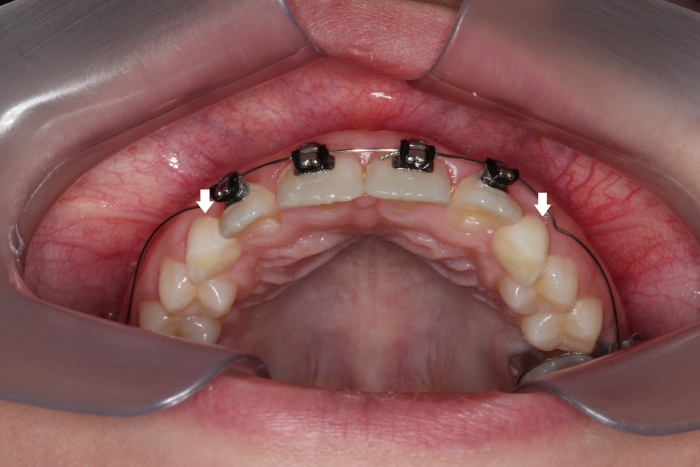

Dentes em tracionamento

Intra oral Final - 2019